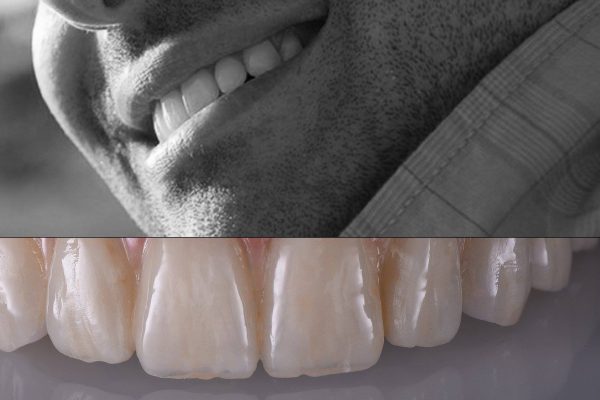

The BioCeramiche, realized by us, are protected in their recipe and manufacturing process by THREE INTERNATIONAL PATTENTS of our exclusive property (n° 01315293 – 01307082 – 01343575 Submitted to the Ufficio Italiano Brevetti) .

We are therefore able to create Unique, Personalized, and Original products